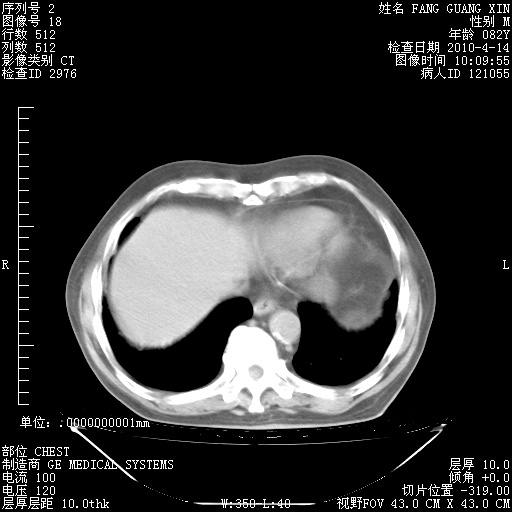

肺部CT平扫未见异常。